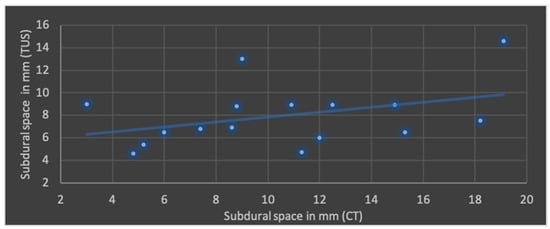

The Pearson’s correlation coefficient (r), including mean values and standard deviation of both modalities in terms of ML shift, lateral ventricular width, subdural space and ICH is shown in Figure 4, Figure 5, Figure 6 and Figure 7.

Figure 6.

Correlation of transcranial ultrasound (TUS) and computed tomography (CT) in terms of subdural space (r = 0.39; p = 0.14; mean value TUS: 7.9 ± 2.7 mm; mean value CT: 10.4 ± 4.7 mm).

The best correlation represented by Pearson’s correlation coefficient was shown in ML shift and lateral ventricular width. The evaluation of ICHs in TUS revealed a slightly weaker correlation, but with a p-value below 0.05, still indicating significance at the standard level. No significant correlation was found in terms of subdural space between both modalities; mean values obtained through CT were higher than those in TUS.

Overall, the timeframe of our study between TUS and CT imaging is situated in the upper range compared with existing works (Table 3). Nevertheless, the qualitatively and quantitatively determined parameters above are comparable with the mentioned studies. In cases of ICHs and subdural space, comparable studies are lacking. This is particularly relevant since postoperative re-hemorrhages in various compartments of the surgical site are among the most common complications following a craniectomy, making an evaluation of the applicability of TUS for assessing re-bleeding important []. In cases of subdural hematomas, no significant correlation was observed in our study. One reason for this could be the pressure exerted on the defect and redistribution of fluid, resulting in a smaller width. Depending on the positioning of the patient, the subdural space also can become smaller, especially with an elevated upper body position, which can influence comparability negatively.

4.3. Technical Limitation and Pitfalls

Although the curved transducer is used routinely in several studies mentioned above, especially when depicting structures through the craniectomy defect, one disadvantage of using the curved transducer is that, particularly in cases of large defects (e.g., large CSF collections), the contact surface may be reduced, requiring increased pressure. This pressure may compress the skin, potentially redistributing underlying fluid and leading to its underestimation. An example of this can be seen in Figure 1e,f, where subdural and epidural CSF collections are evident on CT but only minimally visible on TUS. A relatively high examiner dependency of ultrasound in general is well known [].

Transcranial ultrasound is a safe, cost-effective, and time-efficient method that may become increasingly relevant for imaging post-hemicraniectomy patients. In our experience, transcranial ultrasound was effective in visualizing intraventricular catheter placement, the ventricular system, midline and space-occupying lesions. The present study showed a strong correlation in terms of midline shift, lateral ventricular width and intracerebral hematomas between computed tomography and transcranial ultrasound. Further enhancements in image quality could potentially reduce the overall need for CT scans.